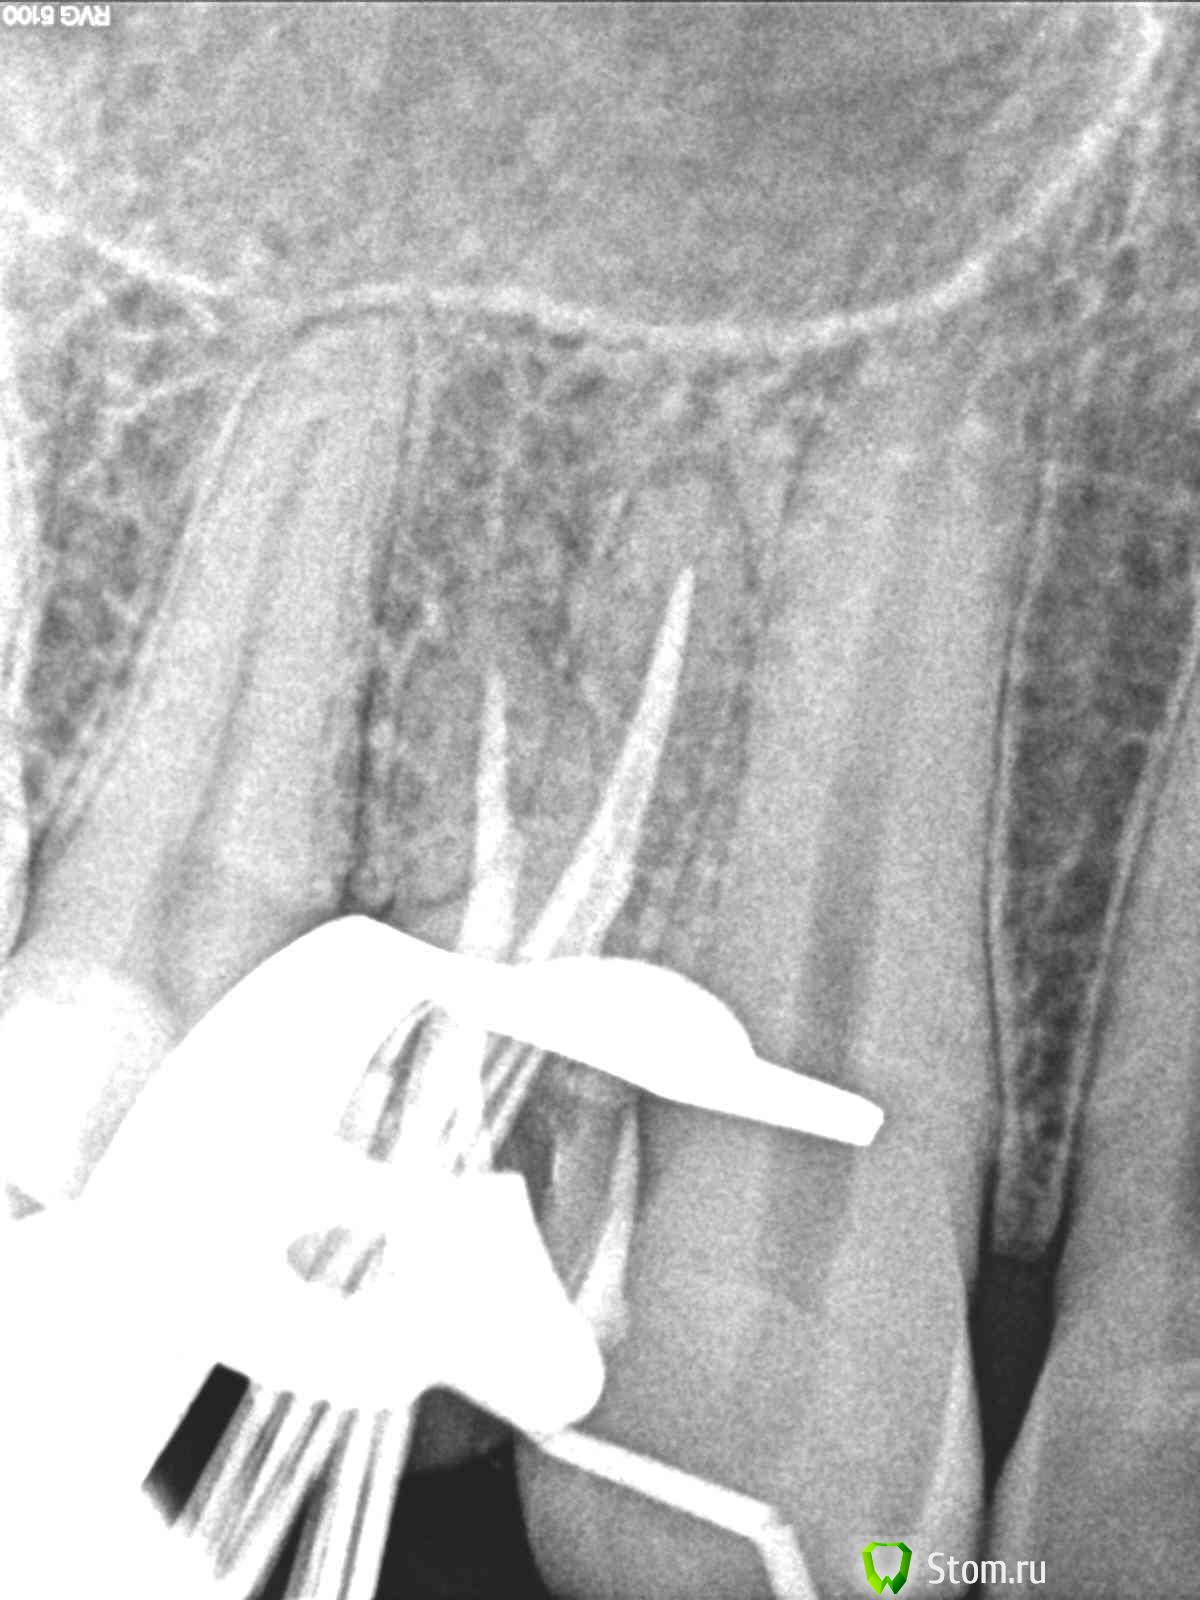

Magdalena Опубликовано 31 января, 2012 Поделиться Опубликовано 31 января, 2012 (изменено) В одном из филиалов стоял микроскоп, случайно узнала, что никто им не работает, забрала себе.)На удаленных зубах потренироваться не успела - попались ситуации, когда скоп был нужен сразу в работе.1. Пациент 66 лет, перелечивание зуба 1.1 под коронку. По КТ - канал запломбирован чуть более 1\2 длины, на верхушке корня очаг разрежения костной ткани с нечеткими границами (КТ фоткала с экрана компьютера, не смогла скопировать ) В первое посещение - распломбировала канал на проходимую длину (в канале гутта), инструмент дальше не идет абсолютно, по КТ хода канала после пломбировочного материала не увидела.Оставила в канале раствор ЭДТА на неделю, пломба Витремер.Во второе посещение еще раз смотрю КТ - смущает меня все-таки такое разрежение, вроде тоооненько прослеживается ход канала. Все отмыла, привезла скоп - на "дне" канала увидела белую точку. Т.к. опыта лечения под микроскопом у меня не было - подумала что это блик, посмотрела под разными увеличениями - все-равно есть, решила пройти по точке УЗ - и сразу же провалилась ( и сердце упало тоже ) Канал при первичном эндо был заступенен.Пломбирование 2. Пациент 35 лет, перелечивание зуба 1.4 под коронку. КТ : каналы запломбированы на 1\2, расширение периодонтальной щели в обл. верхушек корней.щечный каналнебный каналСняла пломбу - в каналах - фосфат-цемент. Сразу привезла микроскоп, распломбировывала УЗ под контролем скопа.Снимок с файлами скинуть забыла Во второе посещение пломбирование, АЛ на этом уровне показывает верхушки Сейчас мне привезли зеркала, специально для микроскопа. В одном наборе стомат. зеркало обычное с увеличением и стомат. зеркало без увеличения, а также маленькие зеркала собственно совсем без зеркальной поверхности... В интернете инфу по ним не нашла, подскажите, плиз, как их использовать. Изменено 31 января, 2012 пользователем Magdalena Ссылка на комментарий